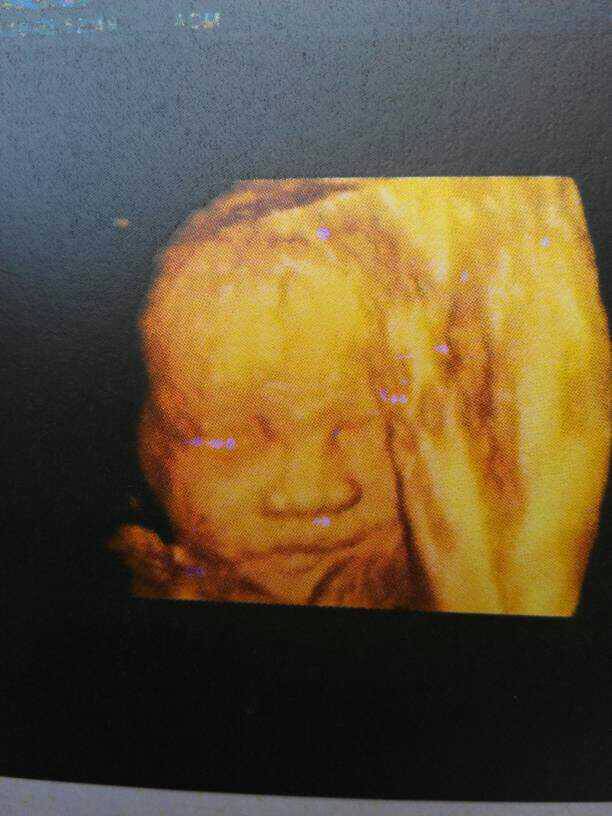

我的宝贝啊,还有两个月咋们就能见面了,好期待 我的宝贝啊,还有两个月咋们就能见面了,好期待 点击展开 陈杏芳-1992 2015-04-21 21:52 为您推荐: 其他回答 看起来,不瘦 后来,我们都变了 2015-04-21 23:03 宝妈,加油。 七秒^钟的记忆√ 2015-04-21 22:43 加油哦,很快了 lihe小宝 2015-04-21 22:25 好孕,,, Your Moon! 2015-04-21 22:12 加油,,, 梓豪麻麻╮(╯▽╰)╭ 2015-04-21 22:04 加载更多 相关问题 还有53天就要和小家伙见面,好期待! 阵痛好像要开始了,等见红了就去医院,好期待和宝宝见面 满满的爱期待我的宝贝,怎能这样?